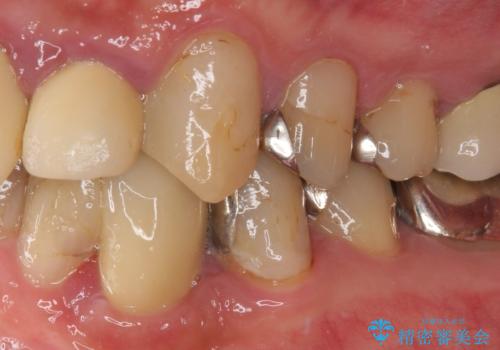

- クラウンがもげてしまった歯が抜歯と言われたとのことで来院された患者様です。

根管治療がされた歯であり、唇側に転位していたため、力がかかったことでクラウンが外れてしまったと判断されました。

麻酔下で歯肉を開いて診察をしたところ、唇側の歯肉縁下に深く歯が欠けている状態でした。

当該歯である犬歯は歯根が長く、安易に抜歯することはおすすめできないため、まずは部分矯正により歯根を引っ張り出し、その後歯周外科処置により歯槽骨や歯肉の状態を整え、最終的にはオールセラミッククラウンにて補綴治療を行うこととしました。